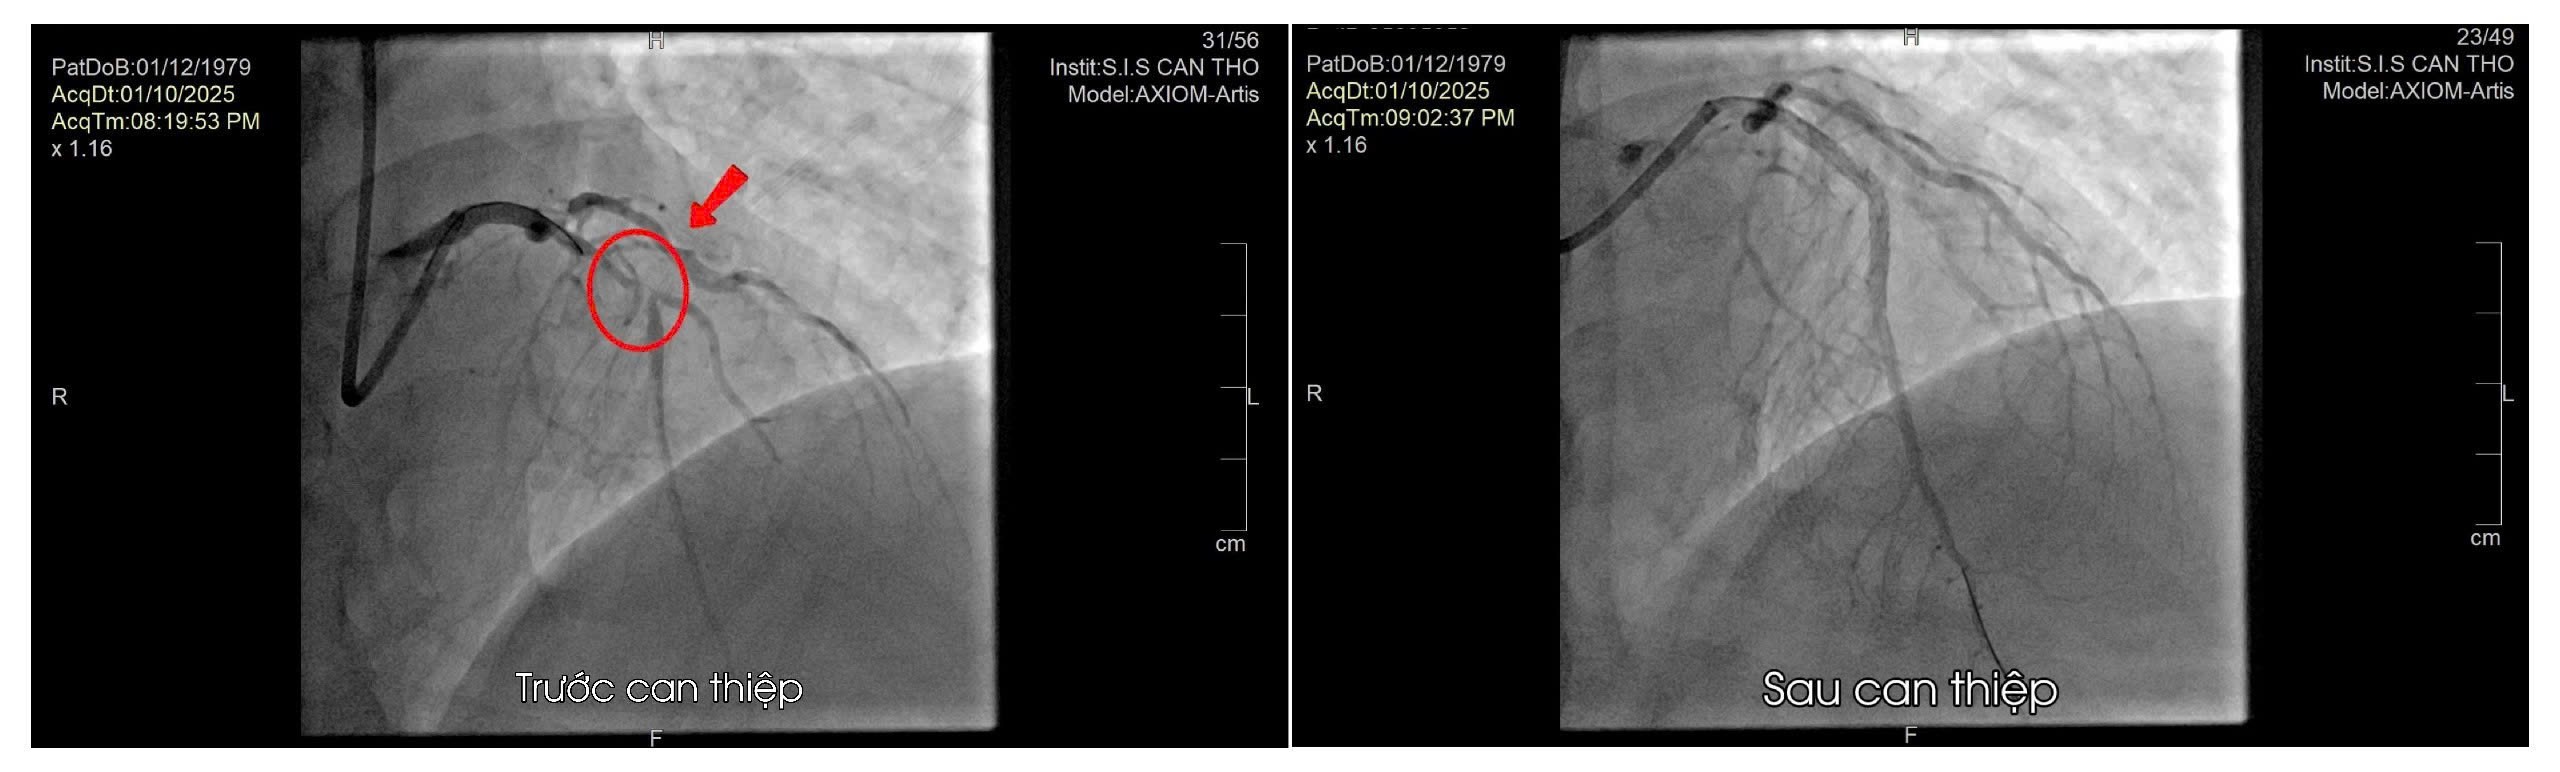

Ê-kíp tim mạch khẩn trương hội chẩn và chỉ định chụp mạch vành cấp cứu, phát hiện tổn thương hẹp rất nặng ở đoạn gần nhánh liên thất trước. Bệnh nhân được đặt stent mạch vành cấp cứu để tái thông dòng máu.

Ca can thiệp diễn ra thuận lợi, bệnh nhân hồi phục nhanh và đã xuất viện trong tình trạng ổn định sau gần 1 tuần điều trị.